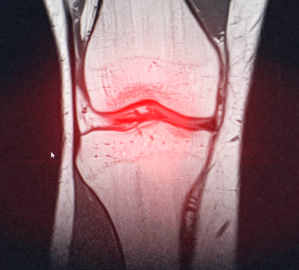

무릎 안쪽 통증 원인 대표적인 9가지와 셀프 마사지 방법에 대해서 알아보겠습니다.무릎은 우리 몸의 중요한 관절 중 하나로, 걷기, 뛰기, 앉기 등 다양한 움직임에 참여합니다. 하지만 무릎에 과도한 부담이 가해지거나 외부 충격이 가해지면 무릎 안쪽에 통증이 발생할 수 있습니다.

무릎 안쪽 통증은 단순한 근육통일 수도 있지만, 심각한 질환의 증상일 수도 있으므로 주의해야 합니다. 무릎 안쪽 통증은 무릎 관절이나 인대, 연골, 근육 등의 손상이나 염증 때문에 발생할 수 있습니다. 무릎 안쪽 통증의 원인은 다양하지만, 대표적으로 9가지를 알아보겠습니다.